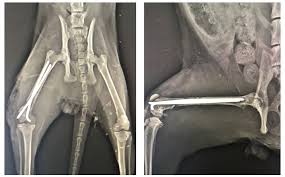

Selecting the appropriate fixation method in cats depends on fracture location and pattern, the cat’s overall health, and the sur...

Femoral fractures in cats are challenging injuries that require careful planning. Successful management balances mechanical stability with biological...

Feline femoral fractures are among the most challenging orthopedic injuries in small animal practices. Successful management demands an understanding...

Quadriceps contracture is a challenging but preventable complication in feline orthopaedic practice. It typically develops after femoral fra...